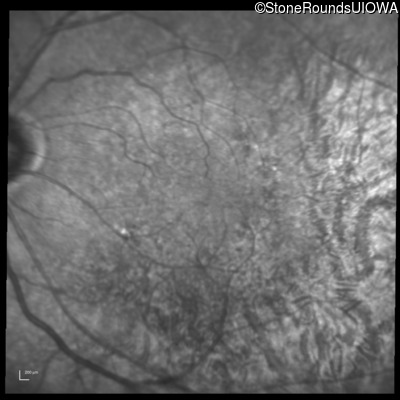

Infrared Fundus Photograph - Left - 20/30 -2

Exemplar